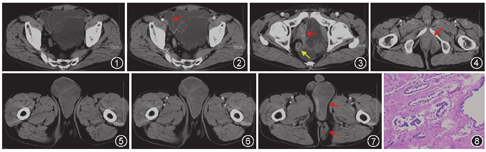

CT表现:CT检查提示盆腔内见巨大不规则形多房囊性肿块,内见大量囊性低密度及少量实性分隔,与前列腺分界欠清,膀胱及直肠受压移位,增强扫描囊壁及分隔可见强化(图1,图2,图3);病变向下突入阴囊及会阴部,局部分叶明显,阴囊内肿块见稍多实性成分,增强后轻度强化(图4,图5,图6,图7)。诊断:盆腔、阴囊及会阴部巨大囊实性占位性病变,侵袭性血管黏液瘤可能。

病理及免疫组织化学表现:盆腔、阴囊及会阴部肿物,盆腔肿物大小15.0 cm×10.5 cm×6.0 cm,阴囊及会阴部肿物大小13.0 cm×10.0 cm×4.5 cm。显微镜下示肿瘤由腺体及囊肿构成,囊壁被覆单层立方上皮,细胞无明显异型,未见核分裂象,不侵犯邻近结构(图8)。免疫组织化学表现:前列腺酸性磷酸酶(PSAP)、前列腺特异性蛋白(P501S)、CD34均为阳性,细胞增殖指数(Ki-67)阳性率约20%,结蛋白(Des)、肌动蛋白(Actin)为阴性。诊断为前列腺囊腺瘤(prostatic cystadenoma,PC)。